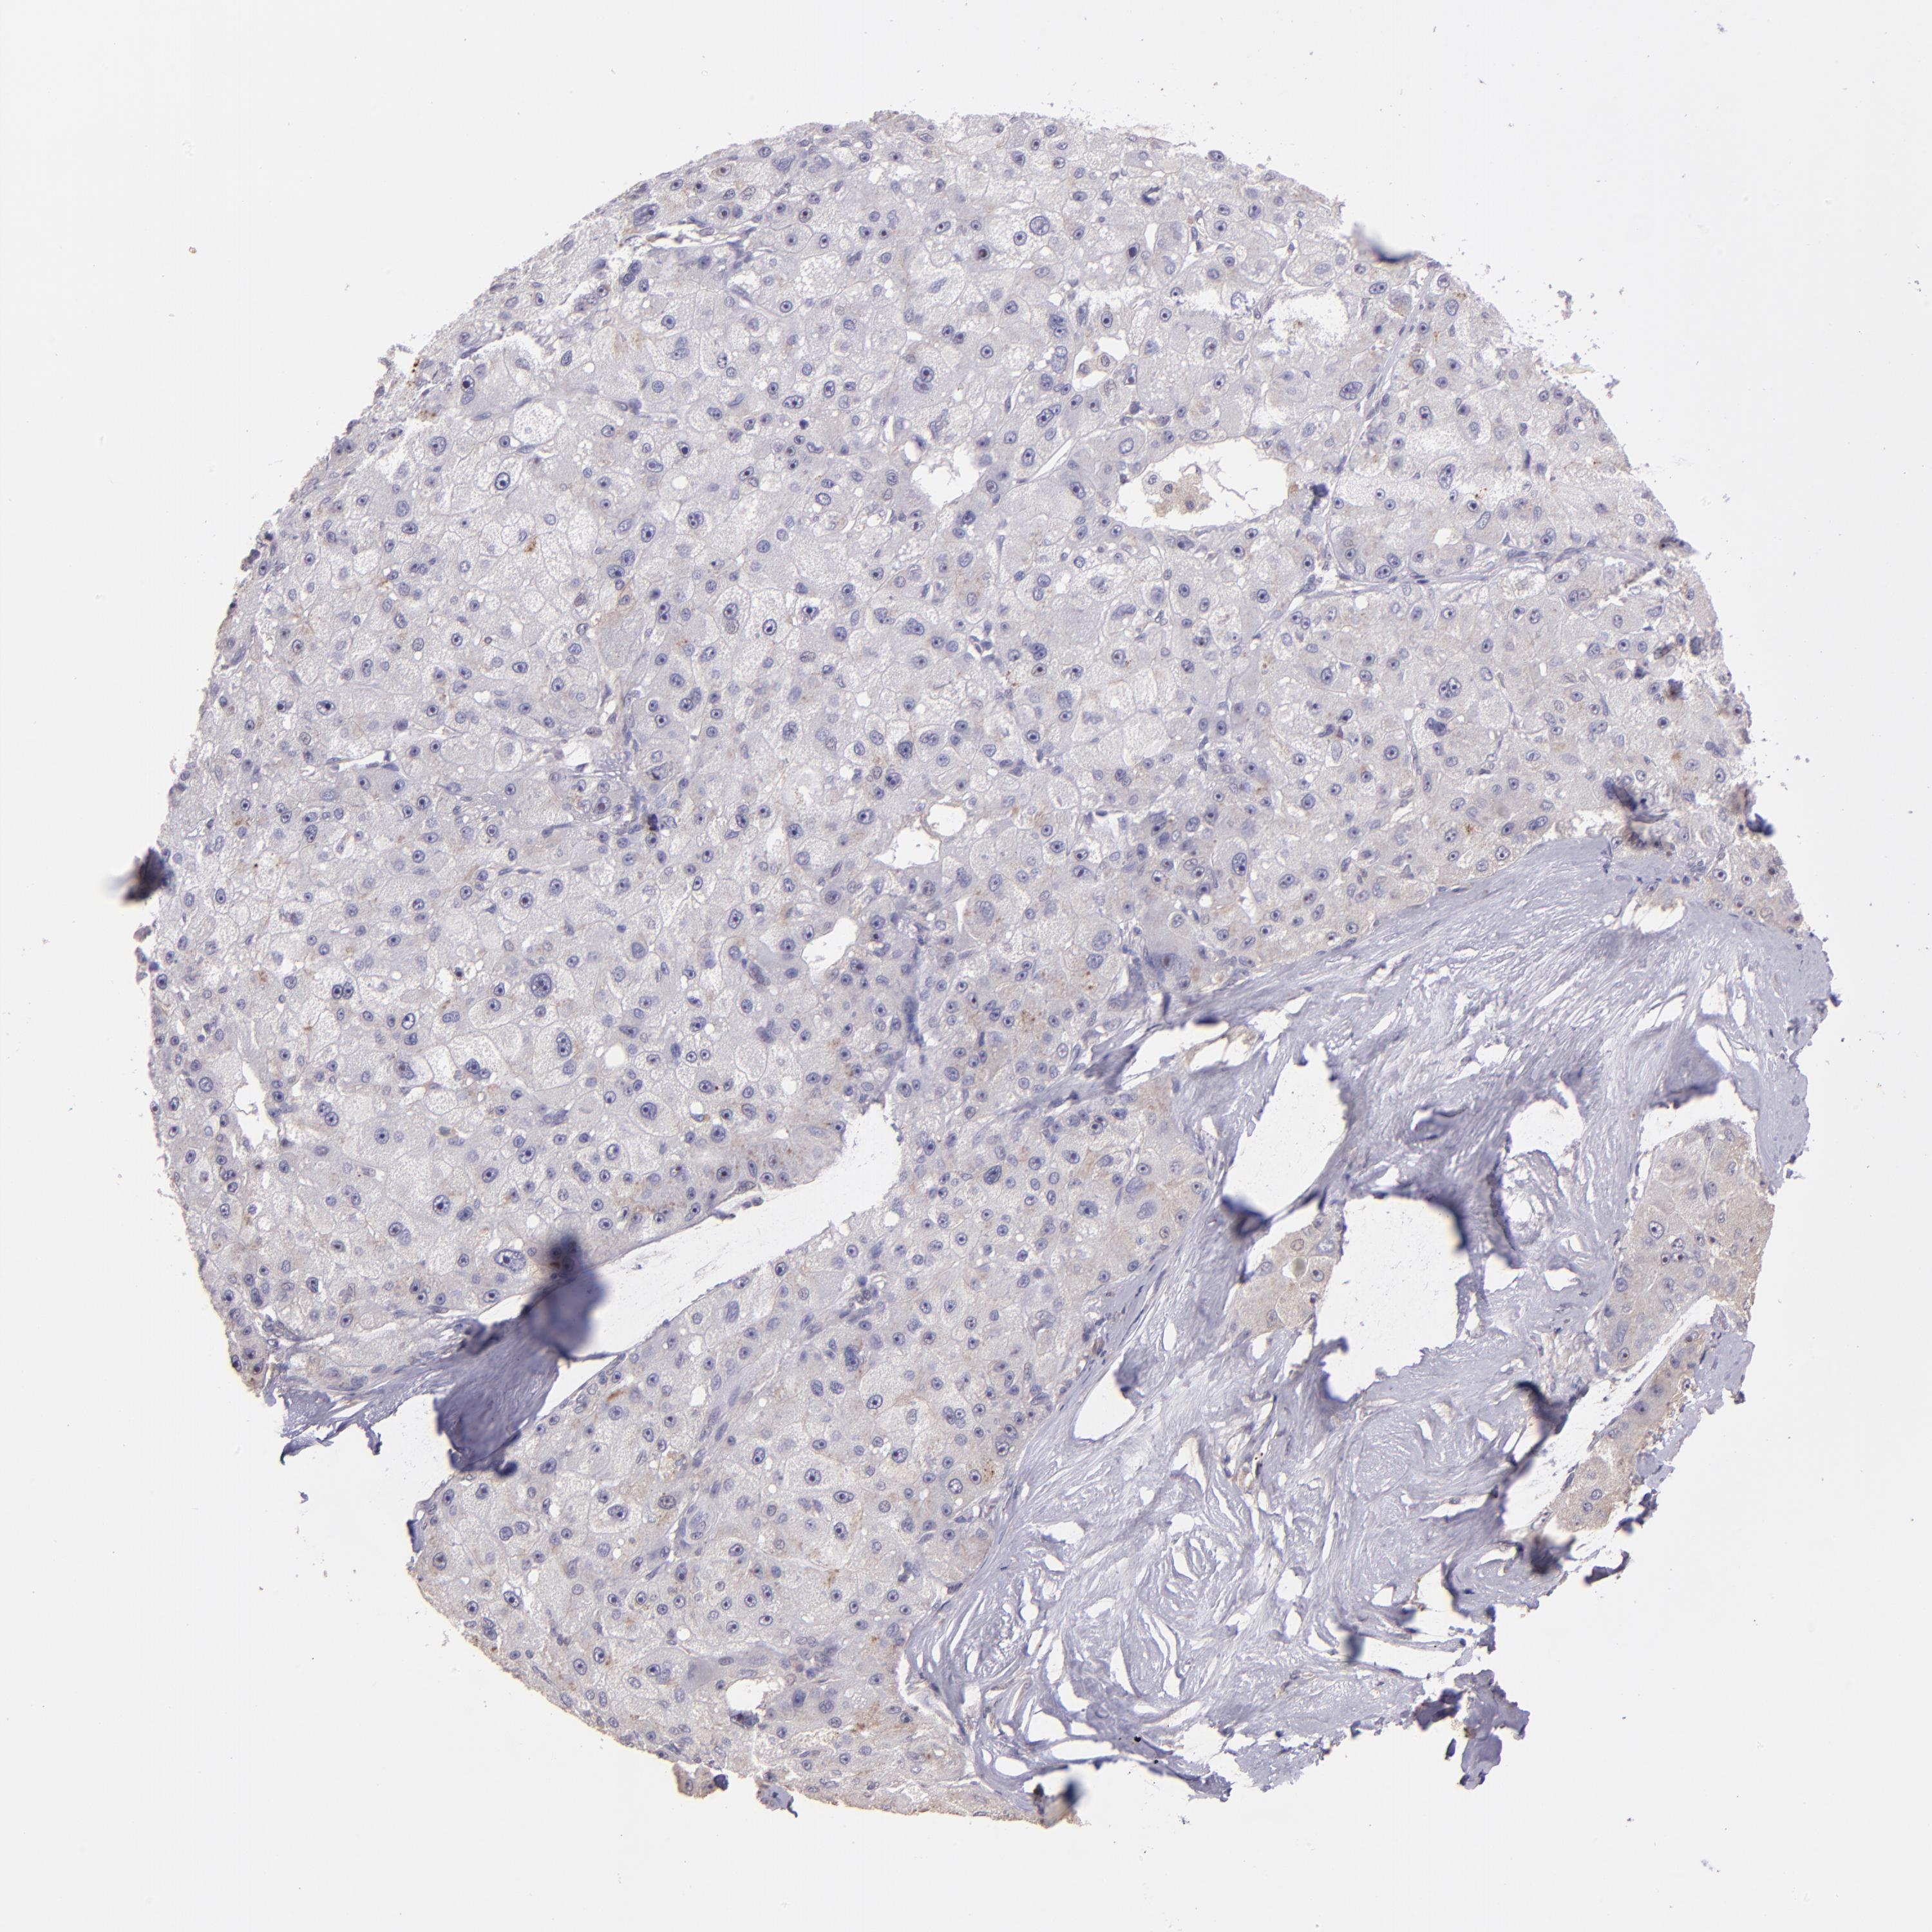

LIVER CANCER - Protein expressioni

A mouse-over function shows sample information and annotation data. Click on an image to view it in a full screen mode. Samples can be filtered based on level of antibody staining by selecting one or several of the following categories: high, medium, low and not detected. The assay and annotation is described here.

Note that samples used for immunohistochemistry by the Human Protein Atlas do not correspond to samples in the TCGA dataset.

Antibody stainingi

Antibody staining in the annotated cell types in the current human tissue is reported as not detected, low, medium, or high, based on conventional immunohistochemistry profiling in selected tissues. This score is based on the combination of the staining intensity and fraction of stained cells.

Each image is clickable and will lead to virtual microscopy that enables deeper exploration of all samples and also displays staining intensity scores, fraction scores and subcellular localization as well as patient and tissue information for each sample.

Antibody HPA001667

Antibody CAB016724

Staining

High

Medium

Low

Not detected

Intensity

Strong

Moderate

Weak

Negative

Quantity

>75%

75%-25%

<25%

None

Location

Nuclear

Cytoplasmic/membranous

Cytoplasmic/membranous,nuclear

Cholangiocarcinoma

Carcinoma, Hepatocellular, NOS